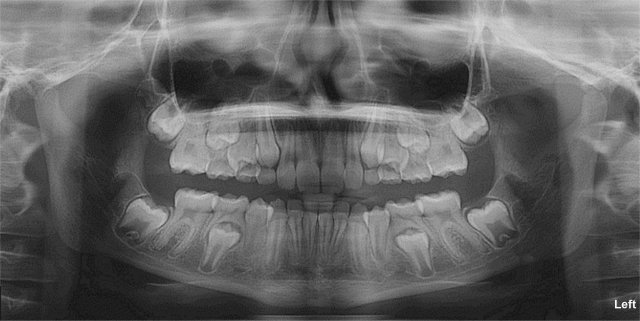

Panoramic 2D X-Ray

The Panoramic Projection

The panoramic is an overview image that is used to show the upper and lower jaws, erupted and unerupted teeth, and to evaluate root alignment, TMJ’s and the sinuses.